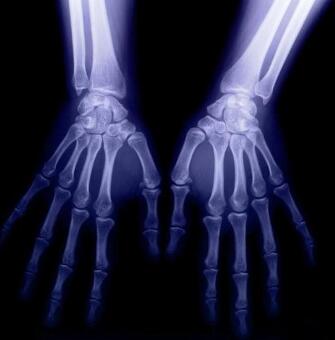

(图:老人初到诊时肉眼可见双手肿胀明显)

(图:X光显示张先生手指关节恢复正常)